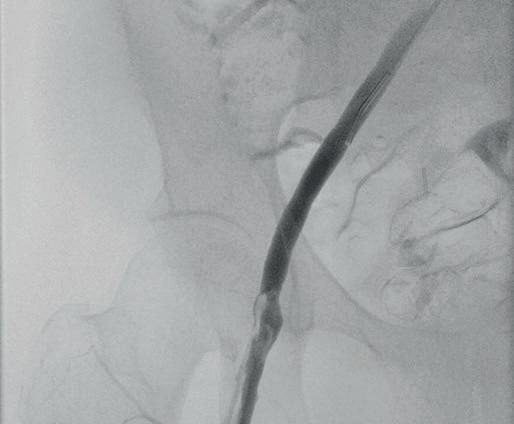

The study was a retrospective review of 66 patients with a median age of 31 who underwent UAE for uncontrolled postpartum haemorrhage at a single, high-volume medical centre between 2014–2022. UAE successfully controlled postpartum haemorrhaging in 62 of the 66 patients (94%). Four patients required hysterectomies to stop the bleeding, all of whom lost at least 2,400ml blood prior to presentation for UAE and showed symptoms of diffuse intravascular coagulopathy, a clotting abnormality that can happen after large-volume haemorrhage due to rapid consumption of clotting factors.

Postpartum haemorrhage is a rare, but potentially deadly complication of childbirth. To stop it, obstetricians will initially use conservative approaches to replace the lost blood or to promote clotting. If these measures are insufficient, hysterectomy is usually performed. Alternatively, interventional radiologists can be brought in to perform UAE, injecting tiny particles into the arteries that supply blood to the uterus using fluoroscopic imaging guidance. Once placed in the arteries, the particles temporarily block blood flow to stem uterine bleeding.